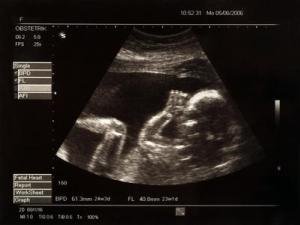

As a fetus grows, it’s constantly getting messages from its mother. It’s not just hearing her heartbeat and whatever music she might play to her belly; it also gets chemical signals through the placenta. A new study, which will be published in Psychological Science, finds that this includes signals about the mother’s mental state.